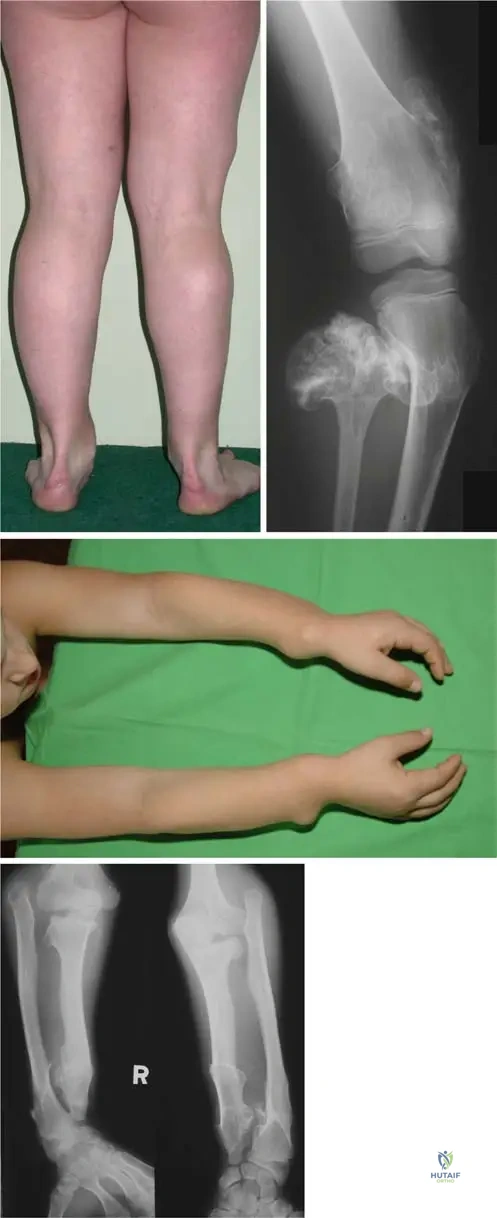

A 7-year-old girl with hereditary multiple exostoses is noted to have progressive bowing of her forearms and ulnar deviation of her wrists. Radiographs confirm multiple osteochondromas in the distal radius and ulna. Which of the following is a common associated deformity seen in HME affecting the upper extremities?

Correct Answer: B

Rationale: Severe deformation of forearms with bilateral elbow dislocation is a recognized complication of hereditary multiple exostoses, as shown in Fig. 1.53d. The bowing of the radius with ulnar deviation of the wrist and subluxation of the radiocarpal joint are also common. While other conditions listed can occur in the upper extremity, radial head dislocation (often leading to elbow dislocation) is a direct and common consequence of the growth disturbances caused by osteochondromas in the forearm in HME.

A 13-year-old boy with hereditary multiple exostoses presents with progressive shortening of his left forearm and increasing ulnar deviation of his wrist. Radiographs show multiple osteochondromas affecting the distal radius and ulna, leading to significant growth disturbance. Which of the following deformities is a common consequence of forearm involvement in HME?

View Answer & Explanation

Correct Answer: A

Rationale: The text mentions "bowing of the radius with ulnar deviation of the wrist, and subluxation of the radiocarpal joint" as common deformities. These findings are characteristic of a Madelung-like deformity, which involves premature closure of the ulnar physis and/or radial bowing, leading to ulnar deviation and dorsal subluxation of the ulna. While not explicitly named "Madelung deformity" in the text, the description perfectly matches its presentation. The other options are unrelated conditions.